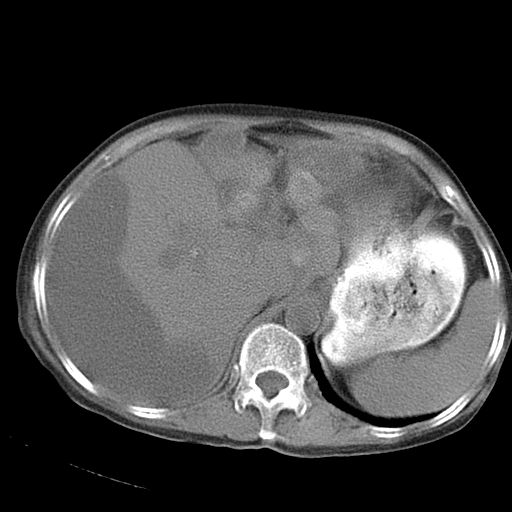

以下是引用dyqct在2006-12-7 21:08:00的发言:[br]考虑:1、肝内外胆管多发性结石伴肝左叶外侧段肝萎缩;[br] 2、右膈下多发脓肿;[br] 3、右侧少量胸腔积液、斜裂积液;[br] 4、左肾囊肿。

以下是引用jiazh在2006-12-7 20:37:00的发言:[br]肝脏周围半狐形低密度影,肝脏表面受压推移,考虑膈下脓肿可能性大;2、右侧胸腔积液

以下是引用拾荒者在2006-12-7 21:44:00的发言:[br]肝内外胆管多发结石,右膈下多发脓肿,右胸膜腔及叶间裂积液,左肾囊肿。[br] [br]